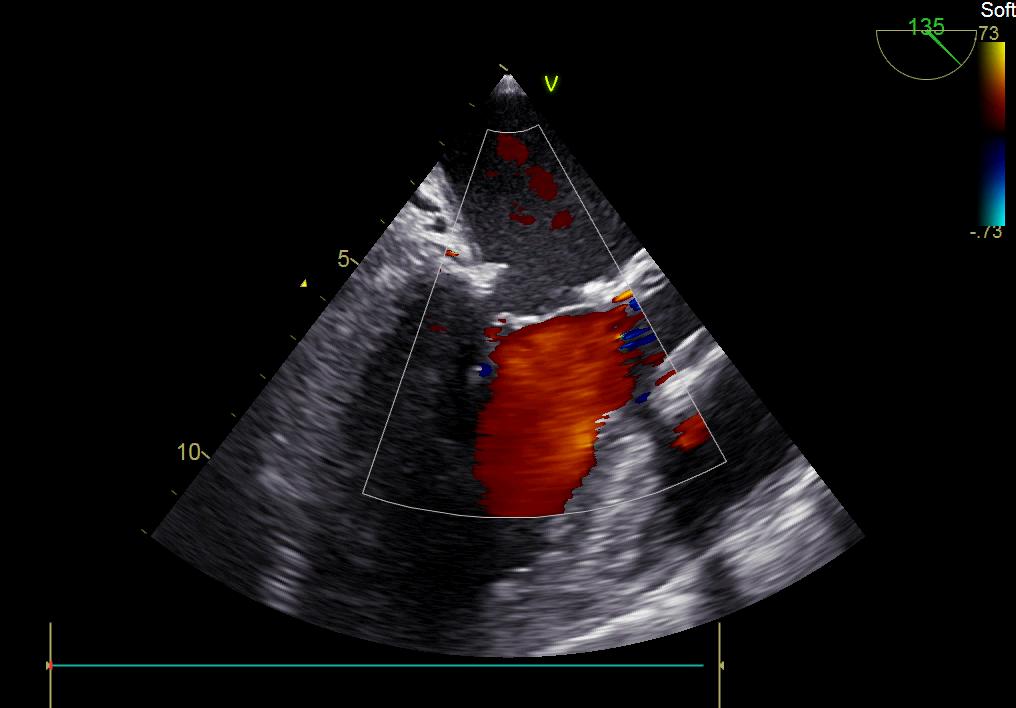

患者何某,42歲男性,因心功能不全入住我院心胸外科,心臟彩超提示二尖瓣后葉脫垂伴有重度返流及心臟擴(kuò)大,在迅速糾正心衰后,手術(shù)便提上日程,心胸外科廖金文主任多次組織全科及兄弟科室討論,在二尖瓣置換及成形術(shù)上,最終決定采取二尖瓣成形術(shù)。為保證手術(shù)安全,討論圍手術(shù)期各個細(xì)節(jié),所謂細(xì)節(jié)決定成敗,因?yàn)樾g(shù)前的細(xì)致全面,加上術(shù)中的一絲不茍及術(shù)后的精細(xì)化管理,患者術(shù)后恢復(fù)順利,健康出院,復(fù)查心臟彩超未見二尖瓣返流。

術(shù)后彩超